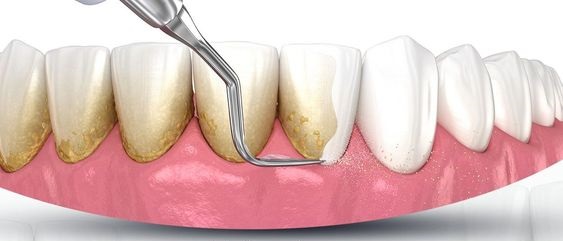

جرم گیری و بروساژ دندان چیست؟

هنگامی که صحبت از جرم گیری و بروساژ میشود، افراد تصور دو درمان جداگانه را خواهند داشت و اغلب این سوال ایجاد میشود که فرق جرمگیری و بروساژ چیست؟ در واقع بروساژ یکی از موارد تکمیلی در فرایند جرم گیری دندان دندان میباشد، که طی این فرایند، دندانپزشکان با استفاده از یک وسیله چرخشی که برسی بر روی آن قرار دارد، یک خمیر مخصوص را به سطح دندان قرار میدهند و اقدام به بروساژ سطوح دندانی می کنند، این کار معمولا بعد از جرمگیری دندان و برای بوجود آوردن سطح صیقلی روی دندان و همچنین حذف رنگها و لکههایی که چسبندگی زیادی ندارند و سفید کردن نسبی دندان، استفاده می شود.

- چرا با جرم گیری و بروساژ دندان ها کامل سفید نمیشود؟

جرم گیری و بروساژ دندان اساسا یکی از درمان های دندان پزشکی است که برای از بین بردن جرم، پلاک ها و رسوبات ایجاد شده بر روی دندان طراحی شده است و شامل سفید کردن و تغیر رنگ اساسی در دندان نمیشود. بعد از جرم گیری و بروساژ دندان ها صاف، براق و تا حد کمی سفیدتر میشوند. از بین بردن لکه ها و تغیر رنگ عاج دندان نیاز به فرایند های شیمیایی و نفوذ به عاج ومینای دندان دارد که شامل درمان های زیبایی مانند بلچینگ و سایر شاخه های زیبایی است که به منظور تغیر رنگ دندان انجام میگیرند.